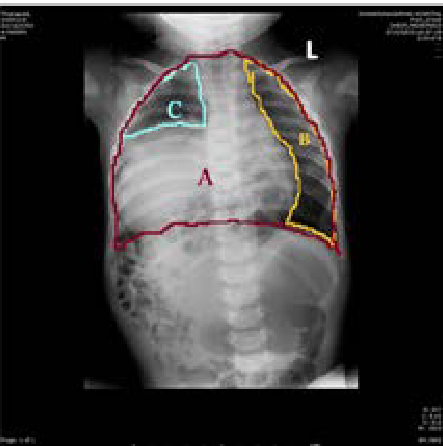

Chest Radiography and Clinical Outcome of Congenital Diaphragmatic Hernia in Single Institution Experience

Napasorn Phutong, Piyawan Chiengkriwate ,Surasak Sangkhathat and Kaimook Boonsanit. 11(12): 03-13.